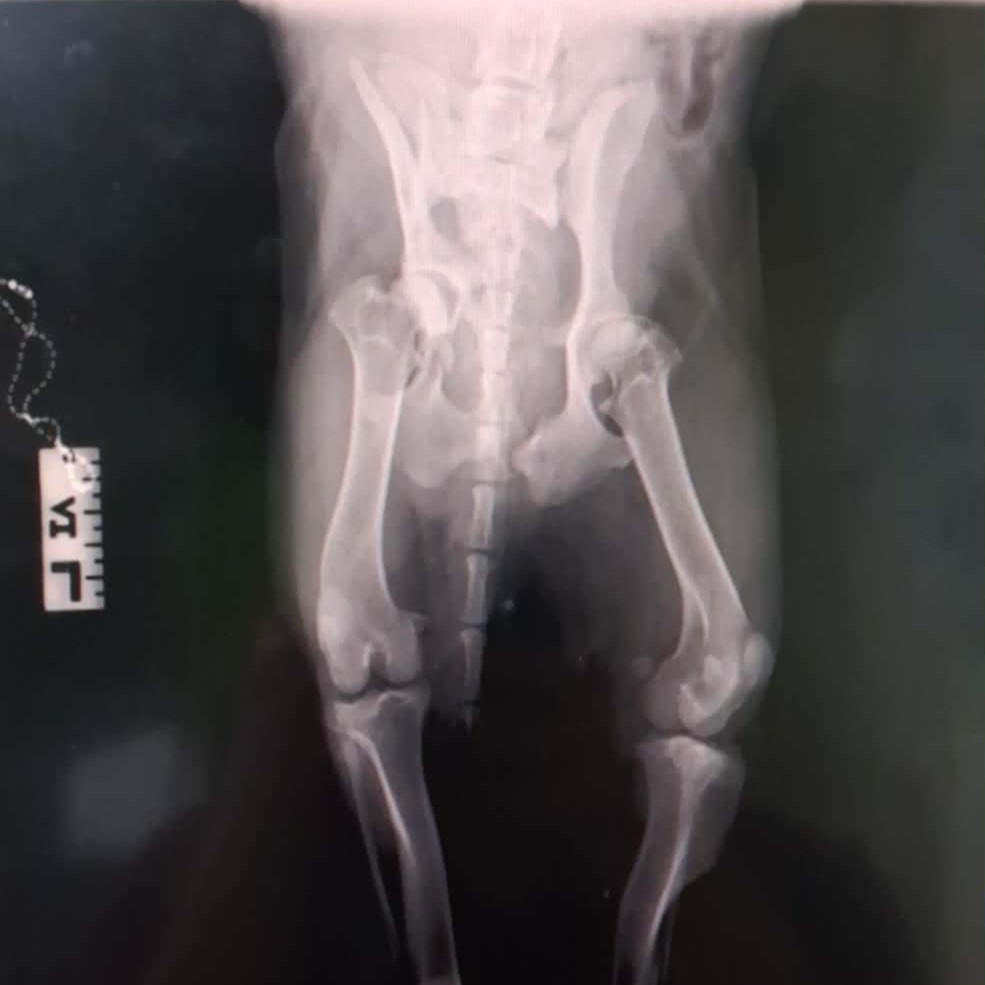

Notfellchen aufgrund von: schwerem Autounfall mit komplizierten Frakturen an mehreren Beinen

Geburtsdatum: ca. 09/2025

Aufenthaltsort: Griechenland / Karditsa